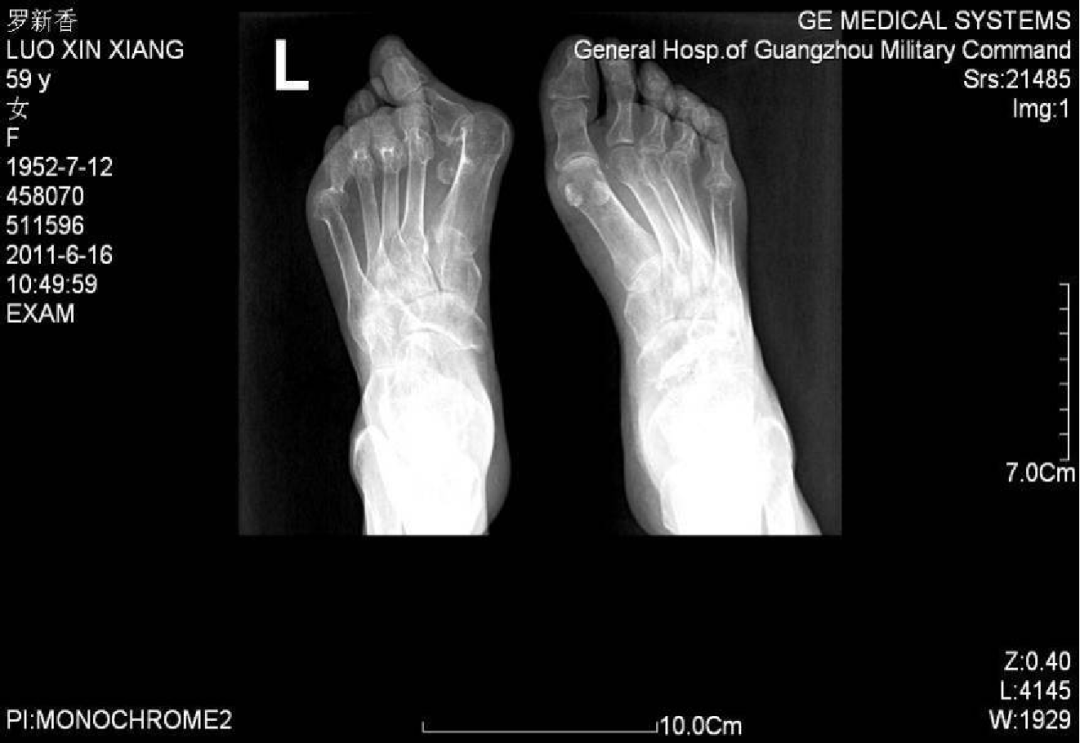

例4:罗XX,女,60Y。

左足:第1-5跖趾关节脱位,足拇外翻。

胼胝体:第一跖骨内侧,第2/3跖骨头跖侧,第5跖骨头跖/外侧。

左足:第2-5趾爪形趾。

右足:第4趾爪形趾,趾间关节胼胝,疼痛。

右足:第5跖骨头跖/外侧胼胝。

CT重建:第1跖骨头破坏。

术式:左足:第1跖趾关节融合+第2-5跖趾关节成形术;右足:第4趾间关节融合+第5跖趾关节成形术